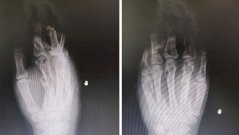

26-летнюю девушку доставили в больницу в шоковом состоянии. Левая рука пациентки попала в мясорубку, почти все пальцы перемололо и сломало. Хирурги сделали невозможное, и спасли кисть девушки.

Травматологи и анестезиологи из Каширской больницы три часа оперировали пациентку. Удалось восстановить все пальцы — девушке обработали раны и установили на ее руке специальный аппарат, похожий на аппарат Илизарова. Пациентке предстоит долгий период восстановления.